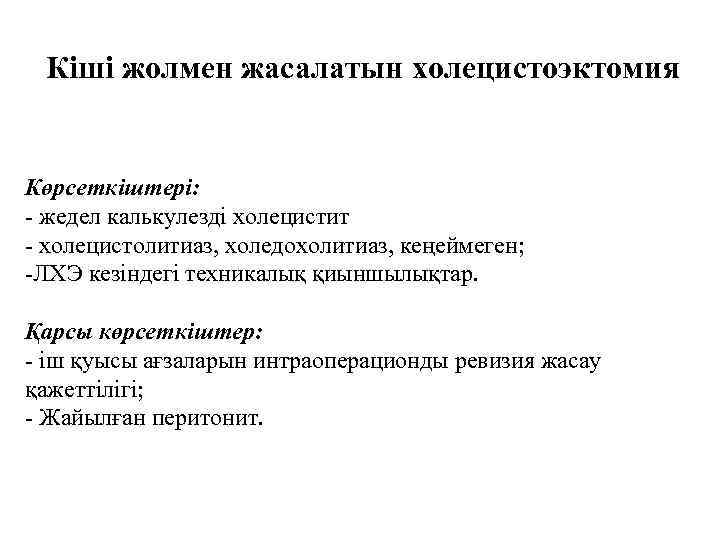

Кіші жолмен жасалатын холецистоэктомия Көрсеткіштері: - жедел калькулезді холецистит - холецистолитиаз, холедохолитиаз, кеңеймеген; -ЛХЭ кезіндегі техникалық қиыншылықтар. Қарсы көрсеткіштер: - іш қуысы ағзаларын интраоперационды ревизия жасау қажеттілігі; - Жайылған перитонит.